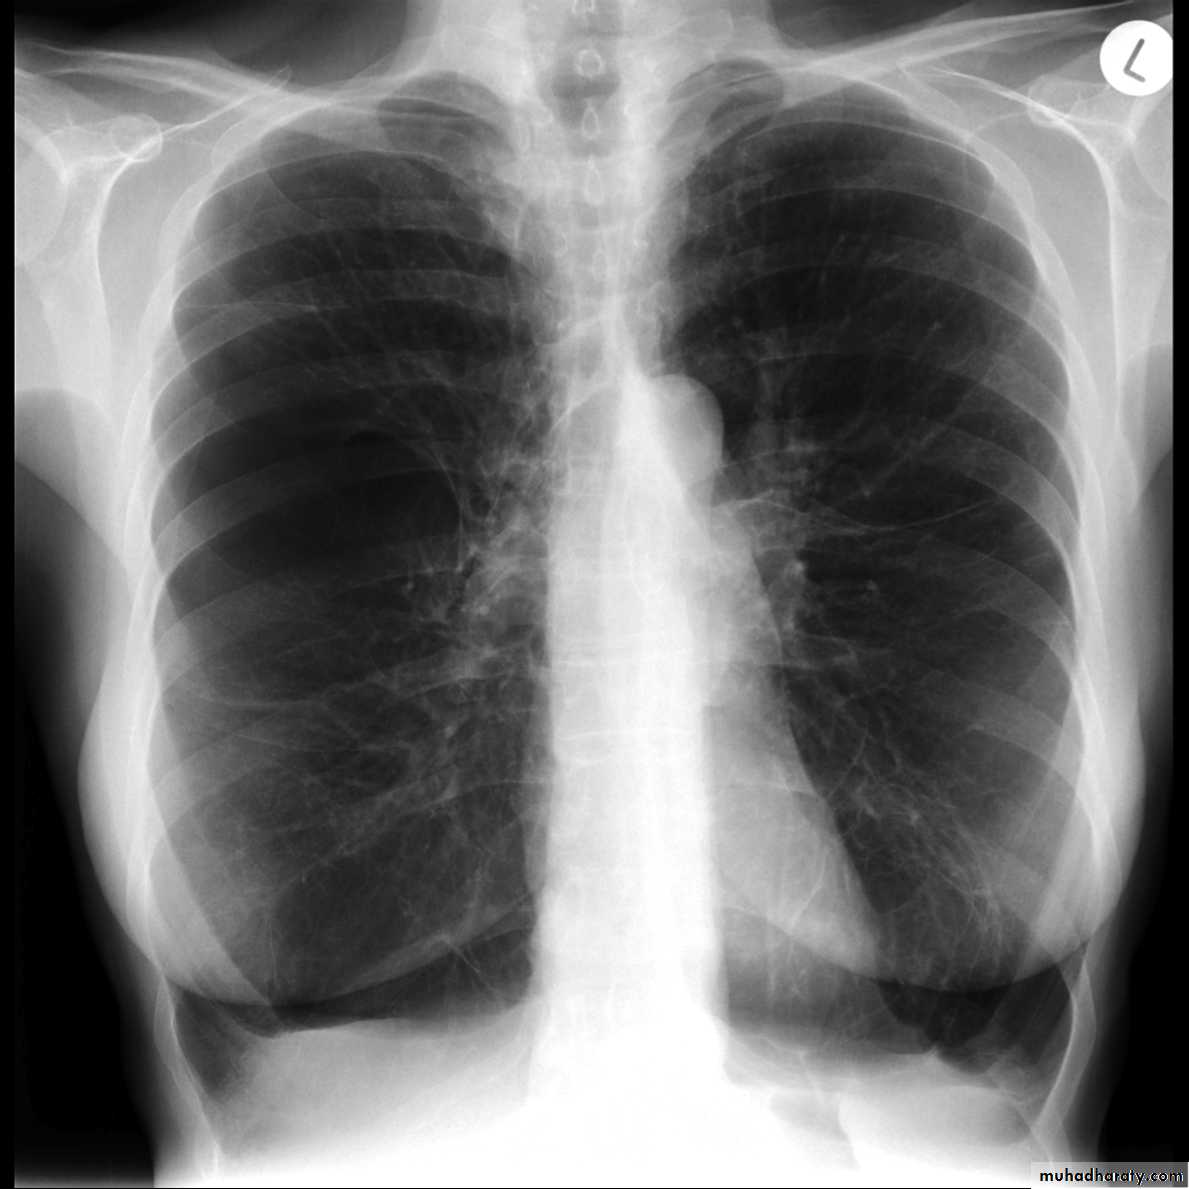

Pleural effusion

50.pleural effusion

51.pleural effusion .